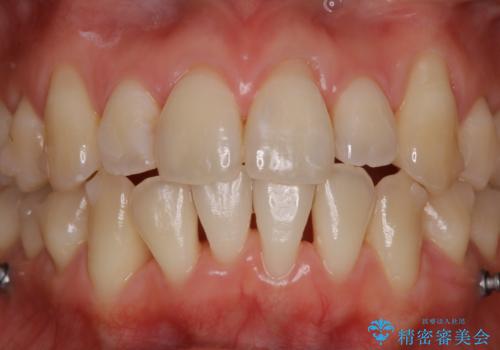

インビザライン中の方 結婚式前にPMTCでステインの除去

- インビザラインでの矯正治療中ですが、結婚式があるため全体の着色・ステインを綺麗にしたいとのことでした。PMTC60分コースを行いました。

PMTC(保険外治療)は、毎日の歯磨きで落としきれない汚れや、コーヒ、紅茶・タバコのヤニなどの着色も除去します。目には見えない歯と歯の間・歯肉の境目・インビザライン中はアタッチメント周囲などに残っているプラーク(歯垢)もしっかり取り除きます。PMTCでは専門的な機械や材料を使用して、徹底的に汚れを除去するため、虫歯・歯周病・口臭予防などにつながります。

またPMTCを行うことで、ご自身本来の歯の色になり自然な明るさになります。

口元が自然な明るさになることで、より清潔感のある印象になるため結婚式・行事やイベント前などにもPMTCを行うはおすすめです。